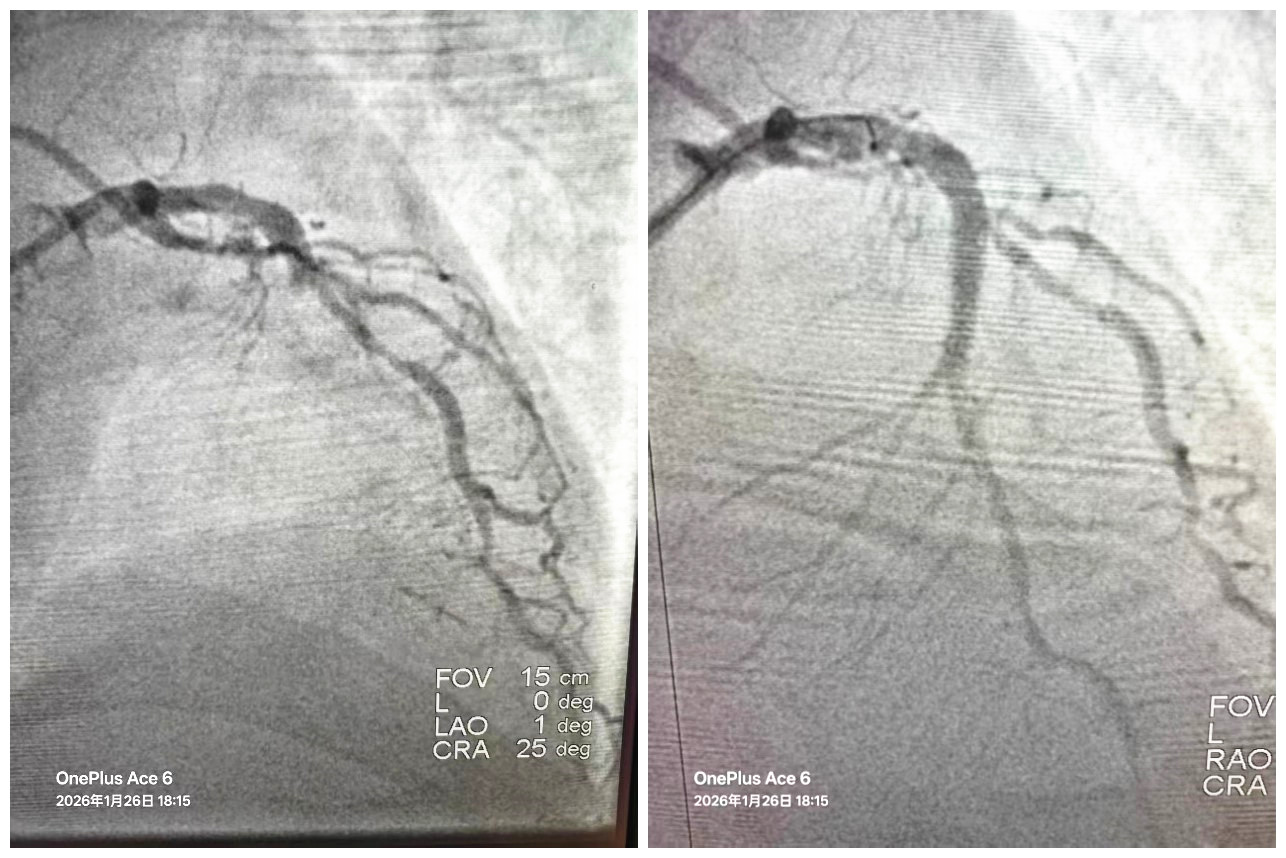

但这仅仅是第一步。急查心电图提示:急性广泛前壁心肌梗死。这是心梗中最为凶险的一种,死亡率极高。医院立即开启绿色通道,导管室激活,一场与坏死心肌赛跑的急诊介入手术立即展开。术中造影显示,蔡先生的冠状动脉前降支近端完全闭塞——这是名副其实的“生命线”中断。心内科介入团队凭借娴熟的技术,迅速开通闭塞血管并精准植入支架,血流恢复,手术成功!

冠脉介入手术前后造影对比,闭塞的前降支成功开通